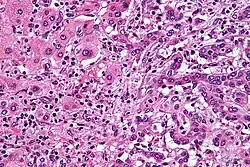

| Micrograph of an intrahepatic cholangiocarcinoma (right of image) adjacent to normal liver cells (left of image). H&E stain. | |

Histologically, cholangiocarcinomas may vary from undifferentiated to well-differentiated. They are often surrounded by a brisk fibrotic or desmoplastic tissue response; in the presence of extensive fibrosis, it can be difficult to distinguish well-differentiated cholangiocarcinoma from normal reactive epithelium. There is no entirely specific immunohistochemical stain that can distinguish malignant from benign biliary ductal tissue, although staining for cytokeratins, carcinoembryonic antigen, and mucins may aid in diagnosis.[47] Most tumors (>90%) are adenocarcinomas.[48]

Pathology

Histologically, cholangiocarcinomas are classically well to moderately differentiated adenocarcinomas. Immunohistochemistry is useful in the diagnosis and may be used to help differentiate a cholangiocarcinoma from hepatocellular carcinoma and metastasis of other gastrointestinal tumors.[66] Cytological scrapings are often nondiagnostic,[67] as these tumors typically have a desmoplastic stroma and, therefore, do not release diagnostic tumor cells with scrapings.